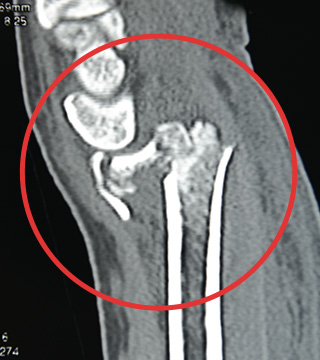

転落して受傷し来院されました。関節面が粉砕して大きくズレた骨折で、適切な位置で軟骨下骨を支持するのが難しいケースです。

このCT画像のような粉砕骨折のケースでも、ハイブリッドロッキングプレートを用いた固定支持が可能です。